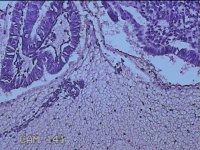

子宫腔内膜组织

性别

女

年龄

44岁

临床诊断

子宫异常出血、甲亢、轻度贫血

一般病史

阴道流血20天,加重1天。

标本名称

大体所见

灰白暗红色不规则碎组织3x2.8x0.3cm一堆。

图4

貌似增生反应子宫内膜。